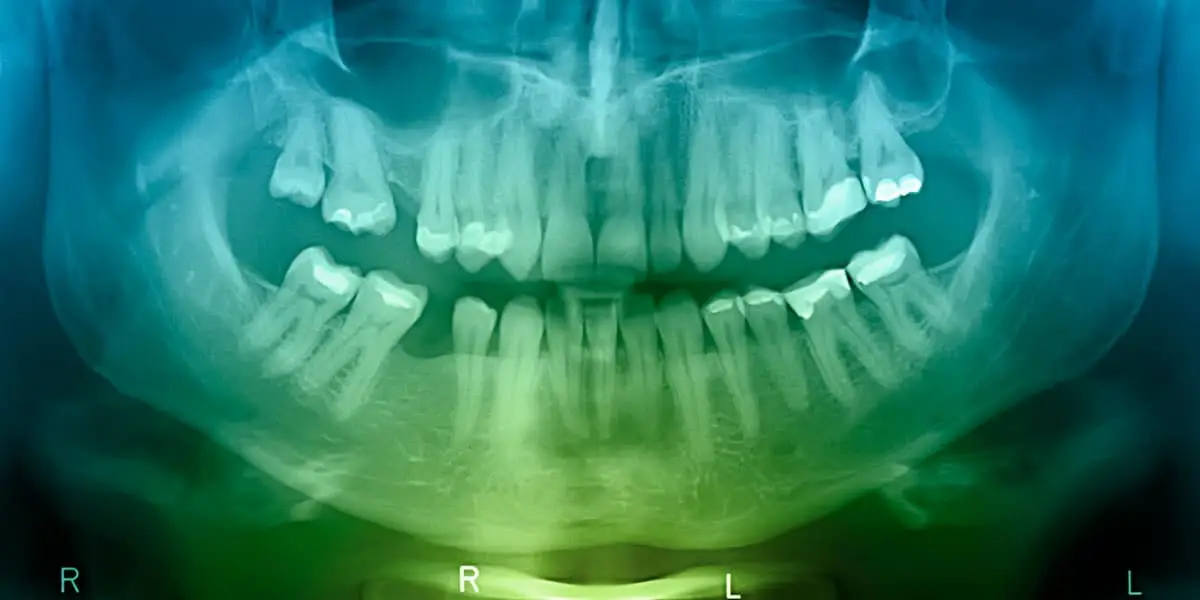

The most frequent bone grafting procedure aims to improve the upper or lower jawbone. This increases the bone's quantity and density, preparing it for the placement of dental implants.

When a tooth is lost, the surrounding bone often deteriorates over time. Patients with insufficient jawbone mass typically aren't suitable candidates for dental implants. Bone grafting is frequently performed to counteract bone loss or enhance existing bone. This allows for dental implant placement once the graft has healed and established the necessary foundation for the implants.

Bone grafting to rebuild jawbone for dental implant support can usually be performed right here in our clinic. Your surgeon might suggest using grafting material from your own bone or from an external source. Synthetic materials can also be utilized to stimulate bone growth. Bone grafting provides proper support for dental implants or prostheses. The healing period before implant placement is generally 4-6 months, though it can occasionally extend beyond that.